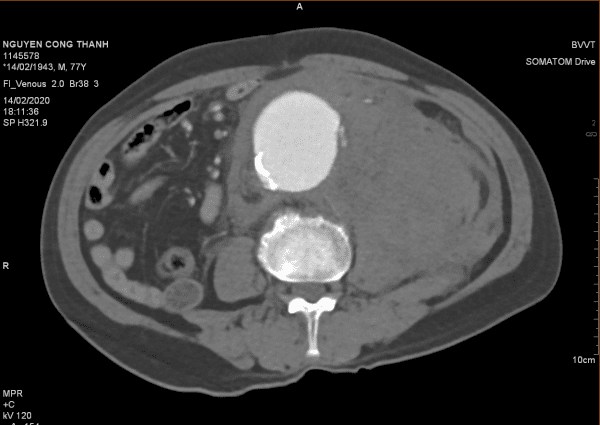

Vỡ phình ĐM chủ bụng

» Thông tin: Nam giới – 77 tuổi.

» Lâm sàng: Đau bụng cấp.